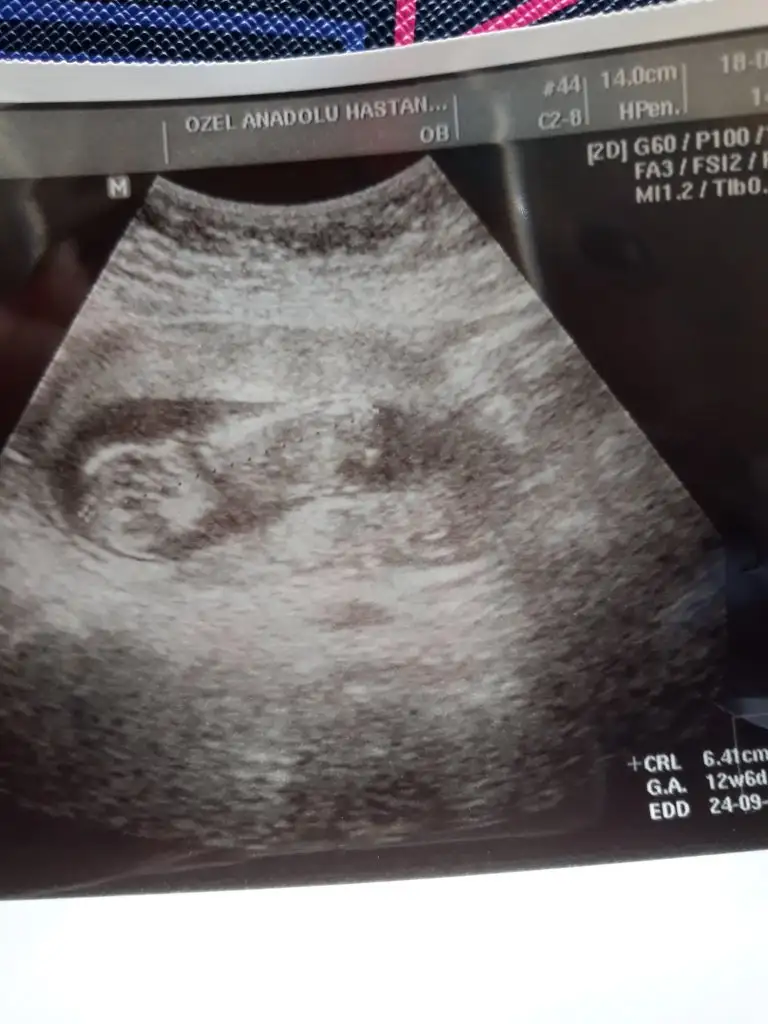

İlk iki foto alttan bakılandan son foto normal daha öncede atmıstım ama cok belli değil demiştiniz bu şekilde bi tahmin olabilirmi Ikra meyra Ikra meyra ☺️

Eklentiler

• 89D640D7-7F11-4AED-A742-98793278443D.webp

89D640D7-7F11-4AED-A742-98793278443D.webp

20,7 KB · Görüntüleme: 57

• 214C707D-EA32-445A-B376-86470776A55A.webp

214C707D-EA32-445A-B376-86470776A55A.webp

23 KB · Görüntüleme: 50

• 836D5433-5295-4294-88E3-6B029A2AAAF2.webp

836D5433-5295-4294-88E3-6B029A2AAAF2.webp

26,6 KB · Görüntüleme: 50